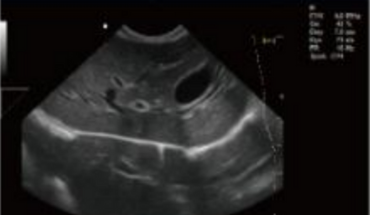

Fonction d'application clinique riche

- B+CF (Images doubles)

- B+CF/DPDI+PW (Triplex)